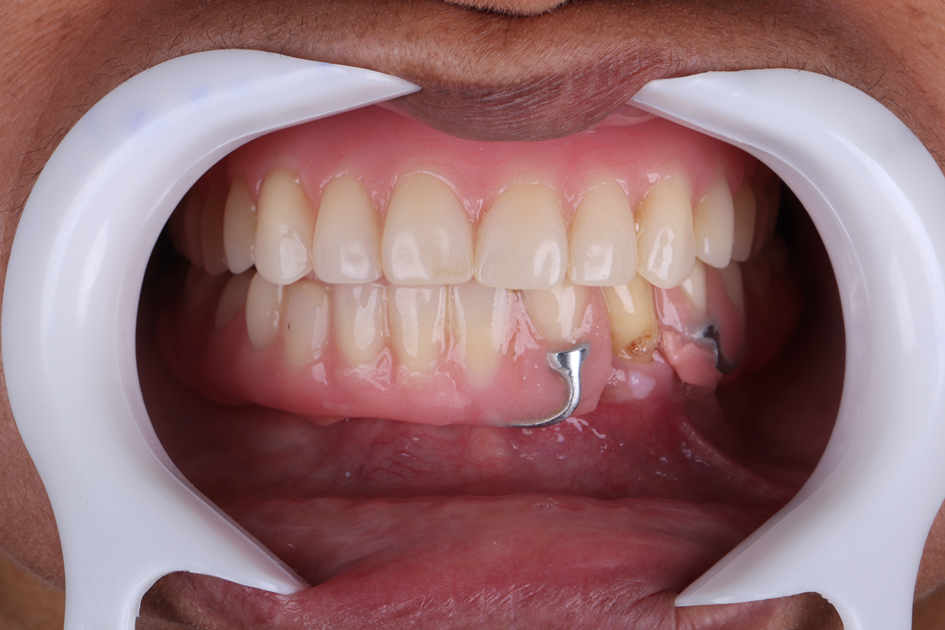

Paciente do sexo feminino, 61 anos, compareceu ao consultório apresentando ausência de todos os dentes da arcada inferior, com exceção do dente 33. Apesar da condição edêntula parcial, apresentava boa quantidade e qualidade de tecido ósseo remanescente. Utilizava uma prótese parcial removível e relatava como principais queixas a dificuldade mastigatória e a insegurança causada pela ausência de dentes fixos.

Considerando o medo relatado em relação ao tratamento odontológico e o desejo por um resultado rápido, optou-se pela reabilitação com protocolo de carga precoce, por meio de cirurgia guiada, utilizando implantes Maestro Cone Morse.

Figura 1 – Foto inicial da paciente em oclusão com prótese parcial removível e prótese total em posição.

Figura 2 – Foto inicial da paciente com a boca entreaberta, com prótese parcial removível e prótese total em boca.